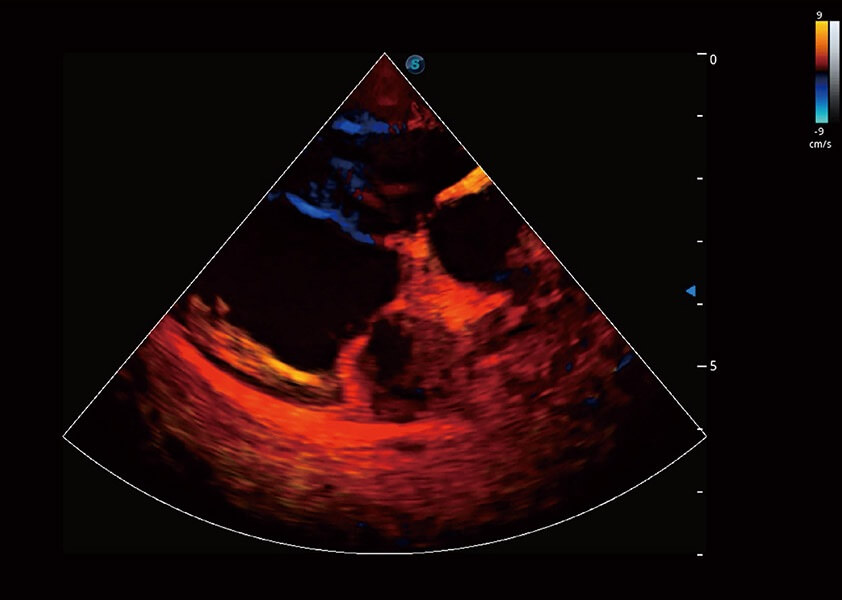

ProPet 60 作為一款高端臺(tái)式動(dòng)物超聲設(shè)備,為動(dòng)物醫(yī)生的日常診斷提供了一系列貼合動(dòng)物臨床需求、解決臨床實(shí)際問(wèn)題的高級(jí)成像功能。憑借全系列高清探頭,滿(mǎn)足醫(yī)生對(duì)腹部、心臟、生殖、淺表、肌骨等成像的所有需求,切實(shí)幫助您提升檢查效率,提高診斷信心。